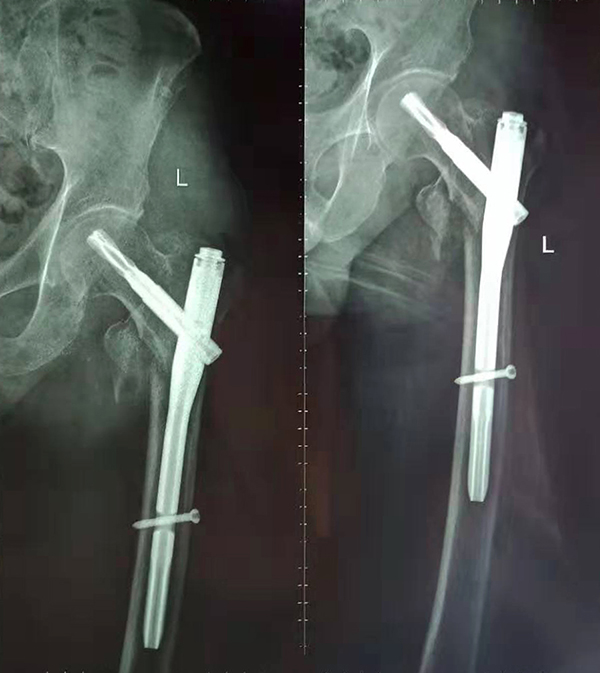

經(jīng)術(shù)前仔細(xì)的檢查和評估,與張爺爺家屬充分溝通,決定了實(shí)施閉合復(fù)位PFNA內(nèi)固定術(shù)的方案,劉鴻程主任說到,該術(shù)式的創(chuàng)傷小、出血少,適合骨質(zhì)疏松病人,術(shù)后解除患者疼痛,可以早期開始活動,便于護(hù)理。

手術(shù)前

手術(shù)后

9月10日上午,骨科順利完成張爺爺?shù)淖蠊晒谴致¢g骨折髓內(nèi)釘內(nèi)固定術(shù)。手術(shù)過程中麻醉平穩(wěn),術(shù)中出血量少,骨折手術(shù)時(shí)間持續(xù)一個(gè)多小時(shí)。